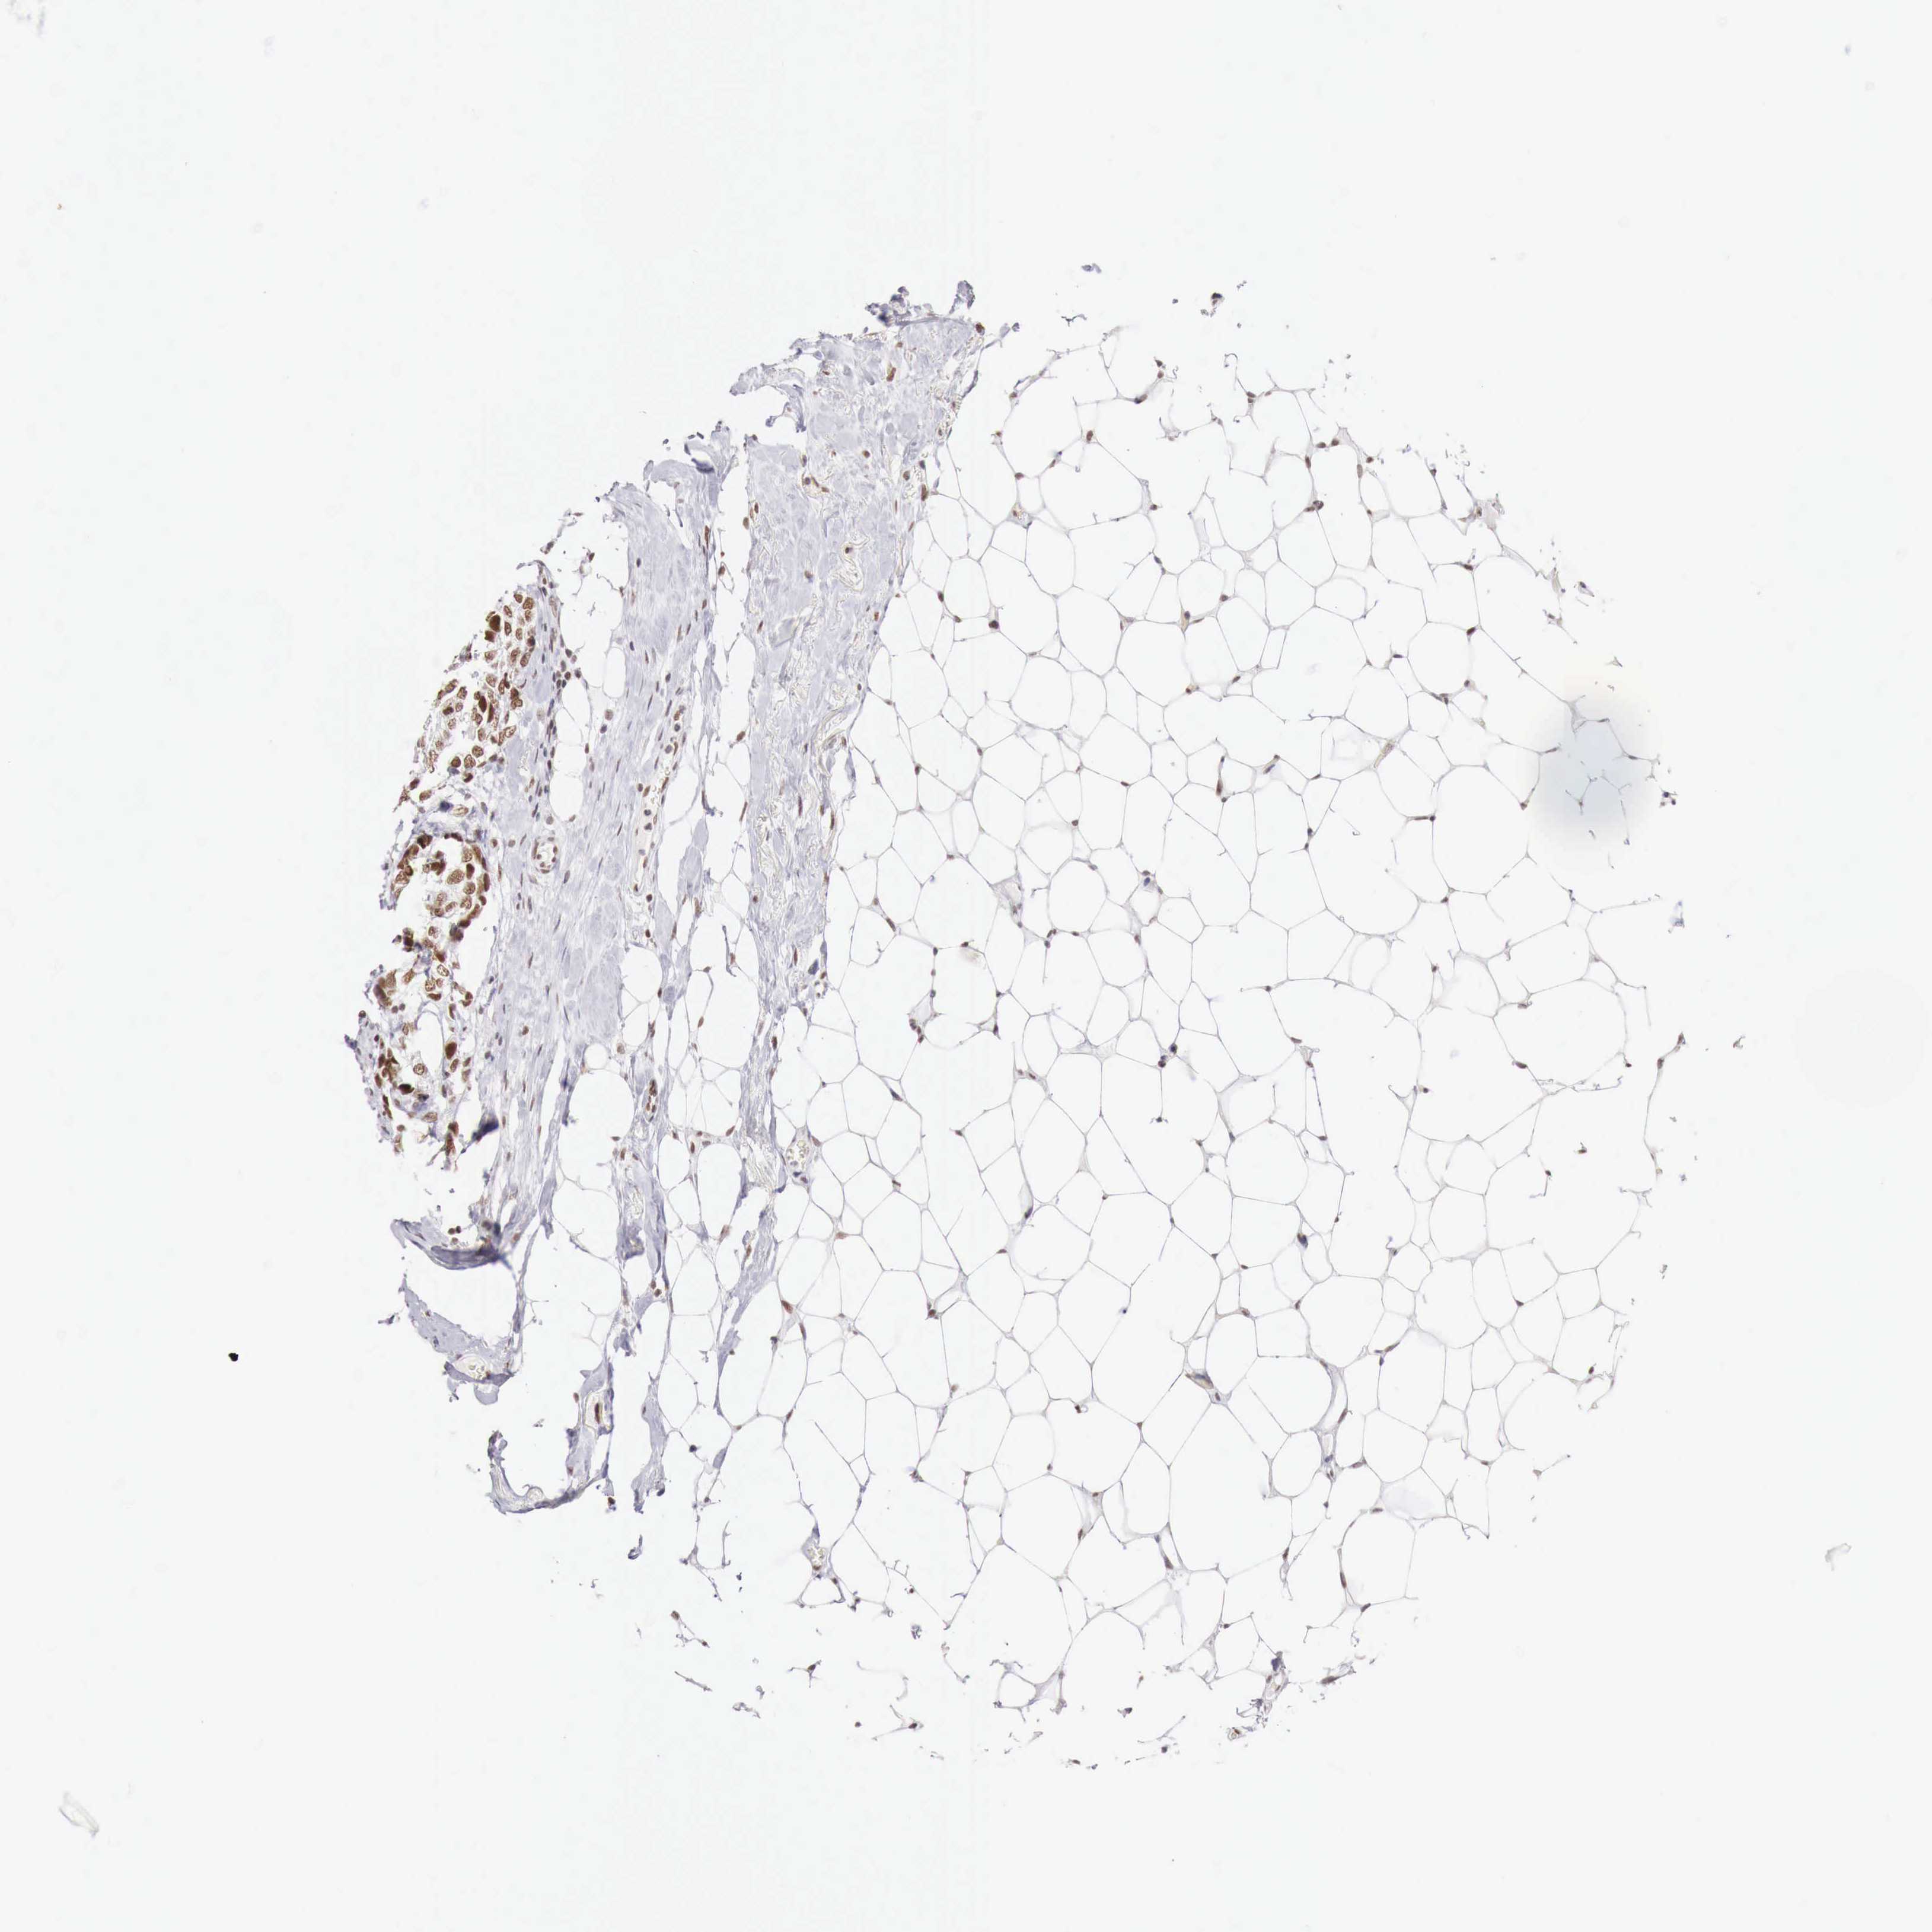

BRCA TCGA BRCA VALIDATION PROTEIN EXPRESSION

ANTIBODIES

AND

VALIDATION